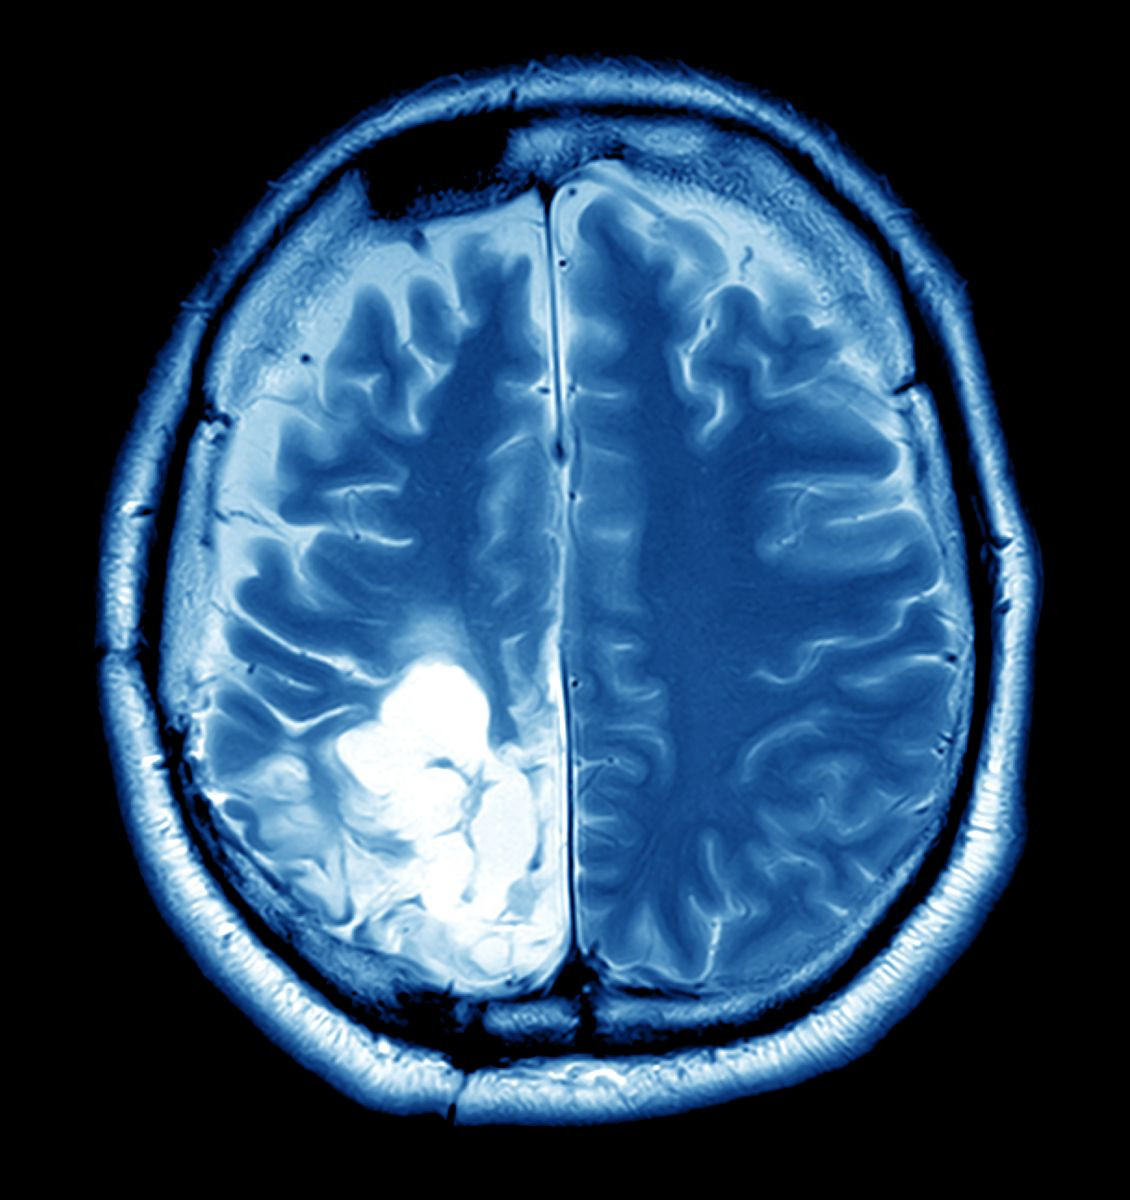

It’s important to note that these symptoms can overlap with more common, less serious conditions. However, if they are persistent, progressive, or unexplained, it is crucial to consult a neurologist. Brain imaging, like MRI or CT scans, can help confirm the diagnosis early.